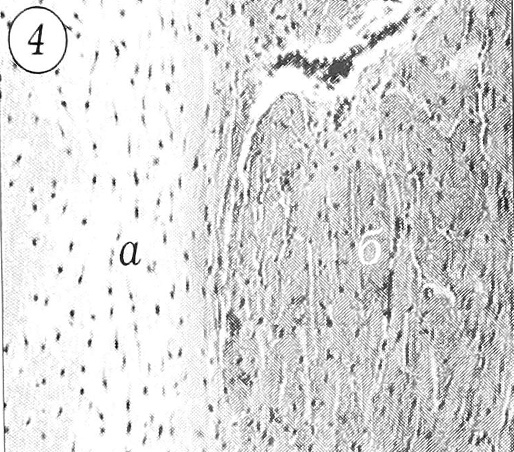

У 7 детей тяжи имели неоднородное строение и представляли собой сочетание гиалинового хряща и соединительной ткани (от рыхлой до организованной) в различных количественных соотношениях (рис. 4). Можно было видеть тяжи, где хрящевая ткань занимала более половины площади исследованного участка, причем граница между хрящом и соединительной тканью, богатой фибробластами и имеющей нежноволокнистую структуру, была нечеткой. В одном из тяжей намечалось формирование пучков, хотя в центральном отделе сохранялся небольшой островок гиалинового хряща. В 2 случаях при сочетании гиалинового хряща и волокнистой неоформленной ткани по периферии тяжа была видна структура, характерная для сформированного сухожилия: участки толстых коллагеновых волокон, богатых фиброцитами, складывались в пучки.

Рис. 4. Тяж смешанной структуры: а — гиалиновый хрящ; б — волокнистая соединительная ткань. Ув. 7,1x9.